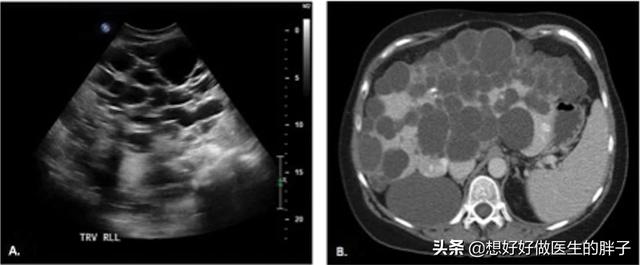

大部分的囊肿对我们的身体并不会产生任何的症状,即使是您体检发现有囊肿,只要不是特别的大,而且不是特别的多,那么就可以忽略不计,不要在心理上老是产生恐惧感,定期体检观察囊肿的变化就可以了。而当一些囊肿长得比较大,对所在的器官造成了挤压,刺激就会产生症状,比如比较大的肝囊肿(下图)。

这样大的肝囊肿会导致患者出现腹痛,有些患者会表现为胃胀、腹胀,还有些患者会表现出来后背的疼痛,这也是比较常见的症状,因为囊肿对周边造成了比较大的压力,而且很有可能导致患者出现黄疸,如此大的囊肿也面临着破裂的风险,如果一旦破裂,破裂的囊液会流入到腹腔内,而且破裂的囊壁有可能会出血,会造成患者出现难忍的腹痛。对于这样造成比较明显症状的囊肿,无论是肝囊肿或者是肾囊肿,以及身体其他部位的囊肿,只要过大,严重影响患者的功能,可能需要外科手术的干预了。比如通过介入手术或者是穿刺抽吸或者是囊肿切除外科的办法来解决巨大的囊肿问题。

另外还有一种问题也是比较棘手的,那就是多囊肝,多囊肾。这是一种先天性的疾病,往往症状随着年龄的增长越来越重,而且随着病情的进展有可能发生肝衰竭或者是肾脏衰竭,因为形成的囊肿过多过大严重的影响了肝脏和肾脏的功能(下图为多囊肝)。